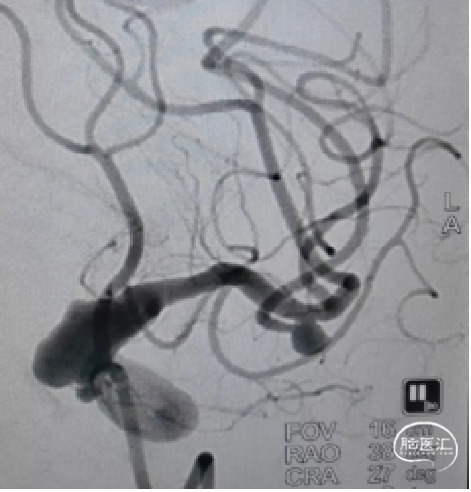

左侧颈内动脉造影:

左侧颈内动脉末端夹层动脉瘤、左侧大脑中动脉分叉部动脉瘤、右侧颈内动脉脉络膜前动脉处动脉瘤。

a.左侧颈内动脉末端夹层动脉瘤形状不规则且囊体较大,大脑中分叉部动脉瘤有一分支发出,这两处动脉瘤相对危险性高,此次优先处理;右侧脉前动脉瘤二期治疗。

b.左侧颈内动脉末端夹层动脉瘤呈不规则长条形改变,脉络膜前动脉在瘤体远端发出,若选用传统的弹簧圈栓塞治疗,则有可能出现分支闭塞,引起并发症,因此考虑使用血流导向装置密网支架覆盖载瘤动脉,避免出现分支血管闭塞。